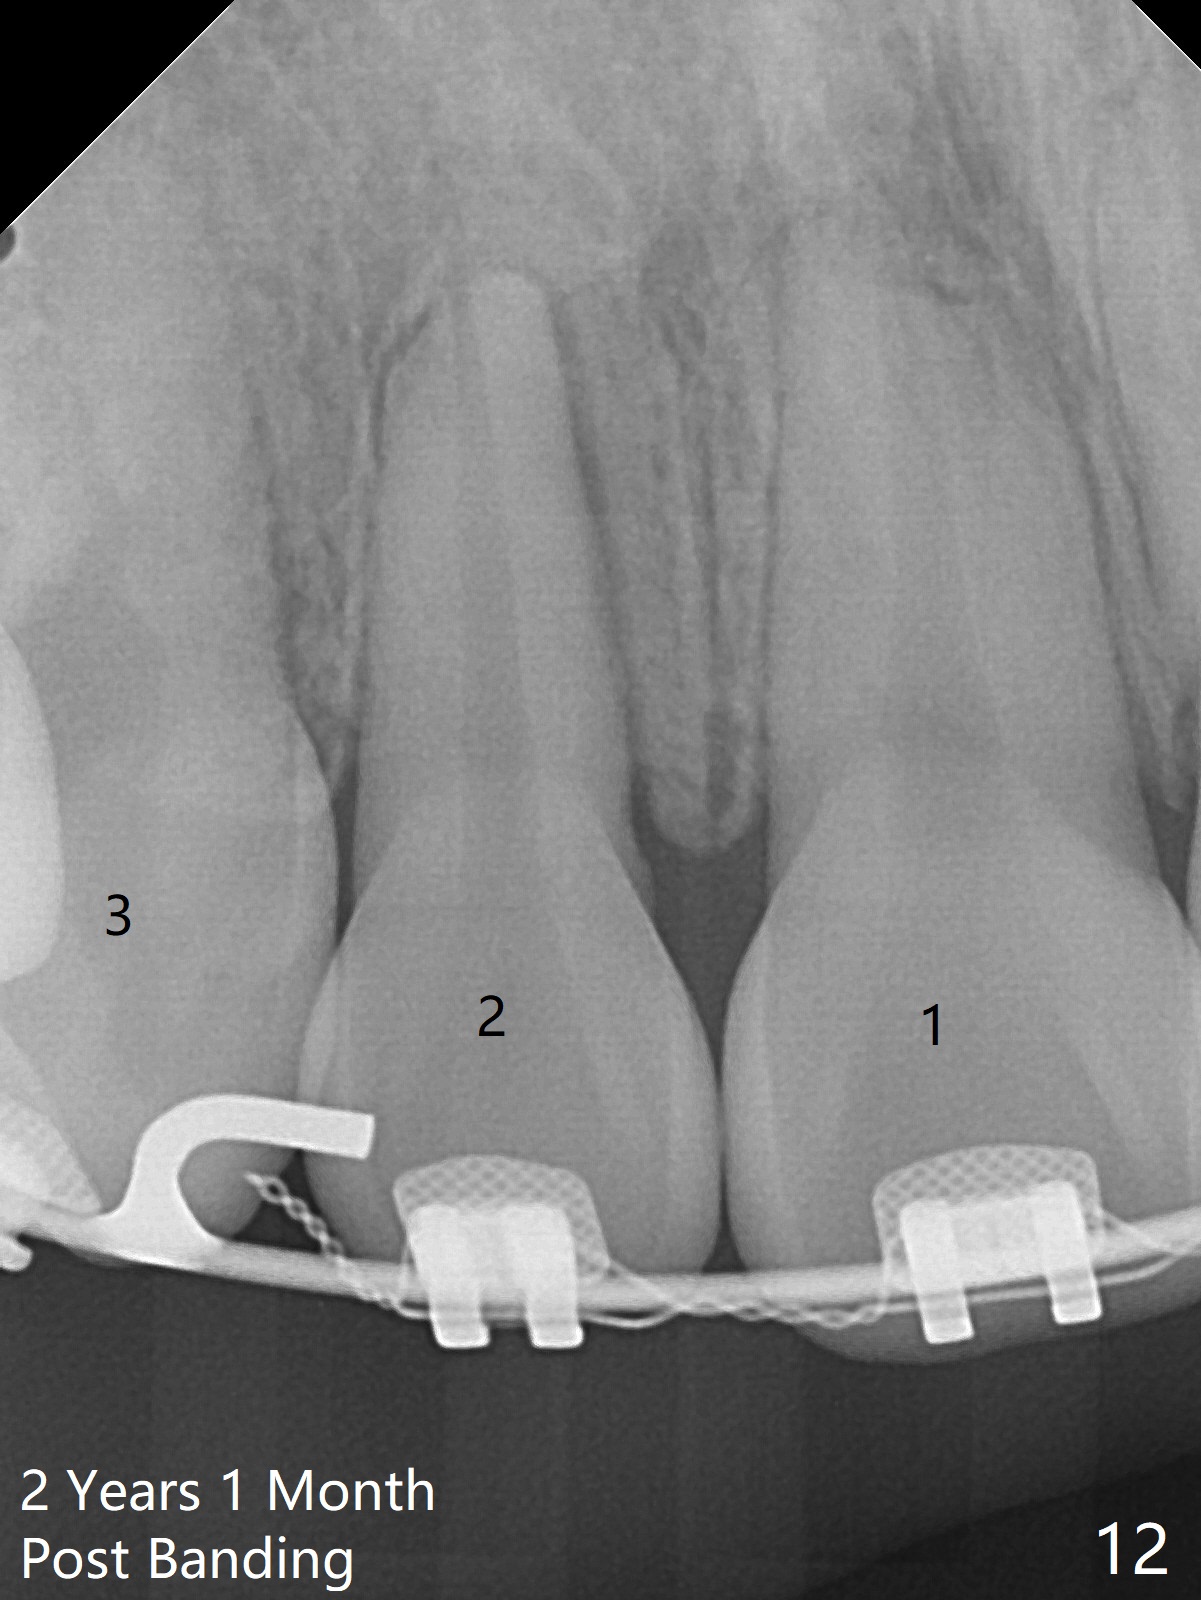

Two weeks post extraction of 4 bicuspids, brackets and bands are placed in 20 teeth (Fig.1-3, 14 niti). No bands are placed at 7s because of short crowns and tight contacts. When 16x16 wires are used, start Class II retraction. The latter is initiated with elastics when 18 ss wires are placed (Fig.4,5). U3s have been distalized with closed springs for 3 months (Fig.6,7). U2s are close to distalization 13 months post banding, 3.5 months post posted wire (Fig,8,9) with overjet (Fig.10). Class II retraction is re-initiated. When the upper incisors are retracted, the anterior overjet remains large. It appears that U6s have been retracted anterior, as indicated by the space between U6/7 (Fig.11), because of no use of U7s as anchors. Brackets are just placed with 18 niti arch wire. They will be retracted distal using the rest of the upper teeth and lower teeth (using Class II retraction) as anchor. There is root resorption of the upper anteriors 2 years 1 month post banding (Fig.12,13).